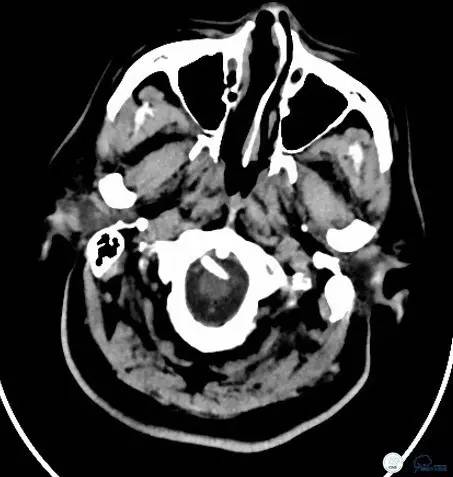

术后给于抗血小板、抗凝、降脂等规范药物治疗。术后24小时复查头颅CT(图14-15):未见出血。

图14

图15